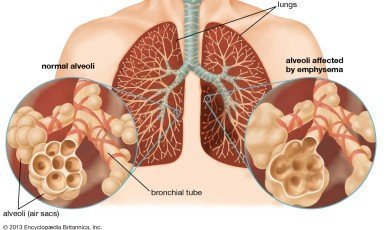

Lung disease

Lung disease refers to disorders that af...